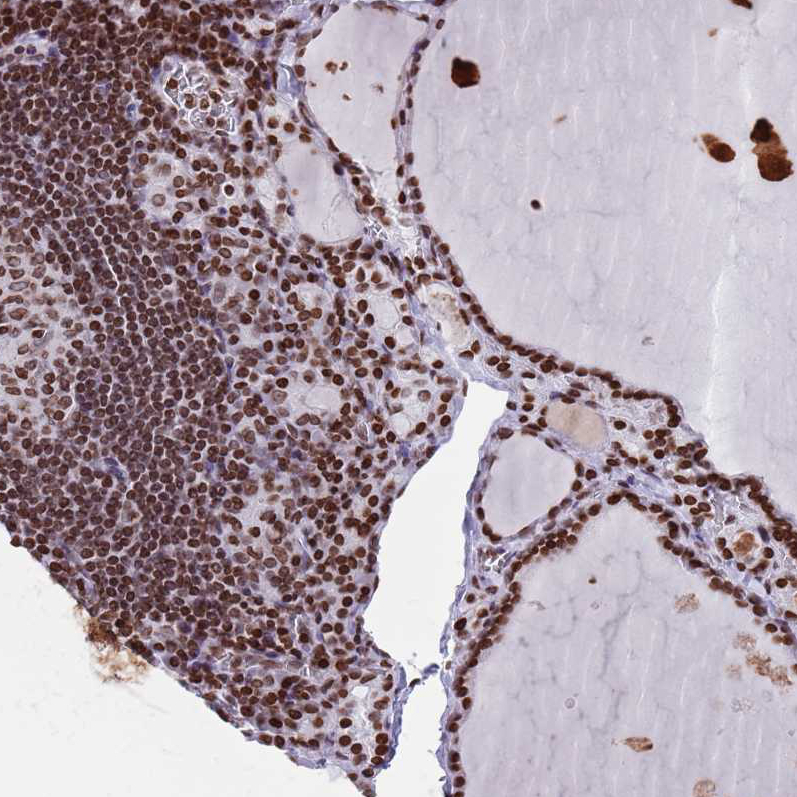

Immunohistochemistry analysis in human thyroid gland and skeletal muscle tissues using HPA048560 antibody. Corresponding HDAC8 RNA-seq data are presented for the same tissues.